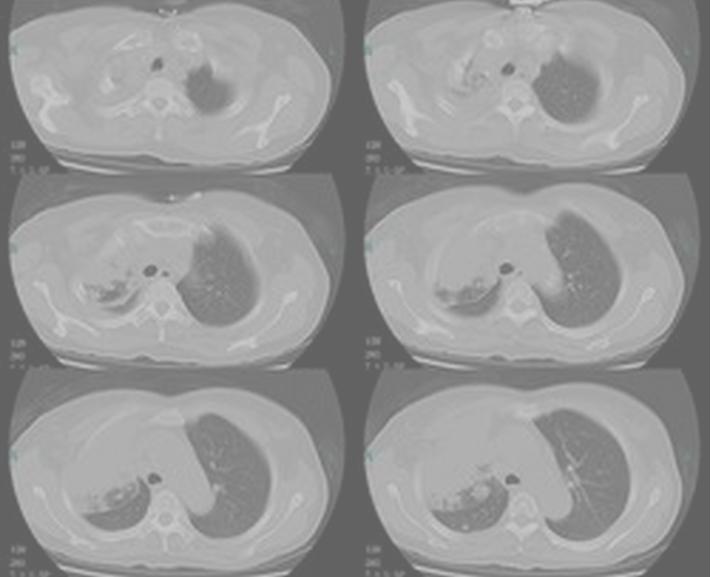

肺癌主要发生在支气管黏膜上皮,根据不同的分类方法,肺癌可分为不同的类型。

按解剖学部位可分为:中央型肺癌和周围型肺癌,而依照肿瘤的起源不同又可分为原发性肺癌和继发性肺癌。

1. 中央型肺癌:发生在段支气管以上至主支气管的肺癌称为中央型肺癌,约占3/4,以鳞状上皮细胞癌和小细胞未分化癌较多见。

2. 周围型肺癌:发生在段支气管以下的肺癌称为周围型肺癌,约占1/4,以腺癌较为多见。